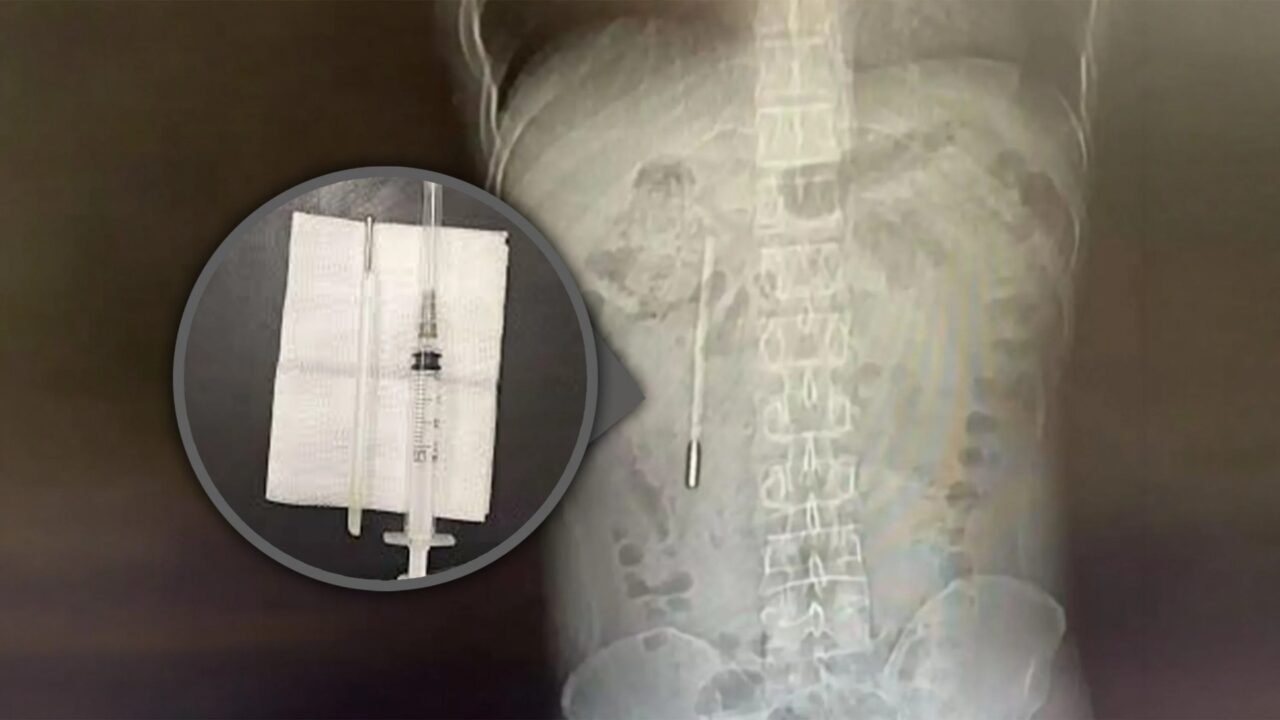

Një ngjarje jo edhe aq e zakontë ka qenë ajo e një të riu në Kinë, i cili kishte jetuar për 20 vite me një termometër në trupin e tij. 32-vjeccari është paraqitur në spital me dhimbje në stomak. Pas ekzaminimeve, mjekët zbuluan se një termometër që ai e kishte gëlltitur kur ishte fëmijë ishte ende brenda tij.

Mediat vendase raportojnë se 32-vjeccari e kishte gëlltitur në fëmijëri termometrin dhe kishte pasur frikë që t’ua tregonte prindërve, ndërsa me kalimin e kohës e kishte harruar fare si episod.

Me kalimin e kohës, ai filloi të shtypte indet e brendshme, duke krijuar një rrezik për gjakderdhje të brendshme. Kirurgët e hoqën me sukses termometrin gjatë një operacioni.